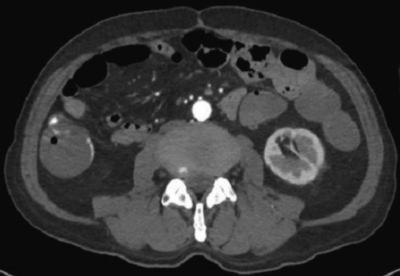

検査所見:血液所見:赤血球 299 万、Hb 9.7 g/dL、Ht 32 %、白血球 12,000、血小板 21 万。血液生化学所見:総蛋白 6.5 g/dL、アルブミン 3.6 g/dL、総ビリルビン 0.9 mg/dL、AST 28 U/L、ALT 22 U/L、LD 277 U/L (基準 176〜353)、γ-GTP 41 U/L (基準 8〜50)、アミラーゼ 80 U/L (基準 37〜160)、尿素窒素 18 mg/dL、クレアチニン 1.1 mg/dL、尿酸 6.7 mg/dL、血糖 128 mg/dL、Na 140 mEq/L、K 4.5 mEq/L、Cl 100 mEq/L。CRP 1.9 mg/dL。腹部単純 CT及び腹部造影 CTを別に示す。

腹部造影CT(遅延相)